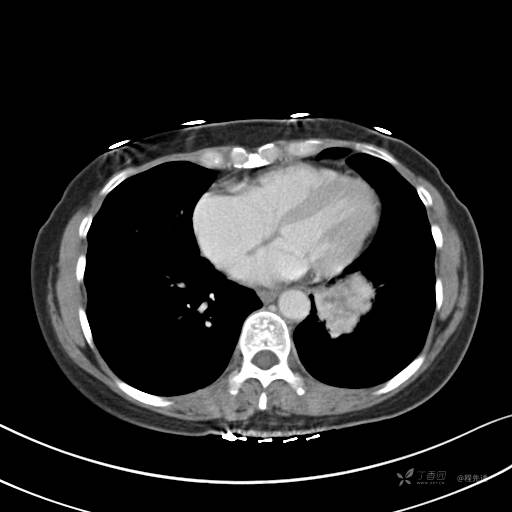

CT平扫

纵隔窗

病灶平扫CT值约31HU